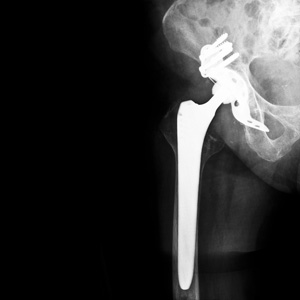

Met het ‘implantatenplan’ wil ze tegemoet komen aan de lacunes die het PIP-schandaal blootlegde. Het is een ambitieus plan dat verder reikt dan enkel borstimplantaten. Ook prothesen (heup, knieën, enkel, discus, enz.), cochleaire implantaten, coronaire stents, pacemakers, hartkleppen, defibrillatoren, endoprothesen, kunstharten en hartmonitors vallen onder de nieuwe regeling.

Al deze implantaten moeten verplicht geregistreerd worden vanaf het moment dat ze op de Belgische markt beschikbaar zijn. De fabrikant of de verdeler moet ze in een systeem registreren. Vanaf oktober 2013 komt er een wettelijk leveringssysteem dat verplicht via de apotheek (officina of ziekenhuisapotheek) zal verlopen. De patiënt die bij de apotheek een implantaat haalt, krijgt (vanaf april 2014) meteen ook het implantaatpaspoort mee. Daarop staan voor de patiënt nuttige gegevens als het soort implantaat, plaats en datum van implantatie, levensduur en geplande datum van verwijdering van het implantaat, reeksnummer en de apotheek die het hulpmiddel heeft afgeleverd. Het paspoort geldt als een bewijs voor de patiënt dat het implantaat het wettelijk circuit heeft doorlopen.